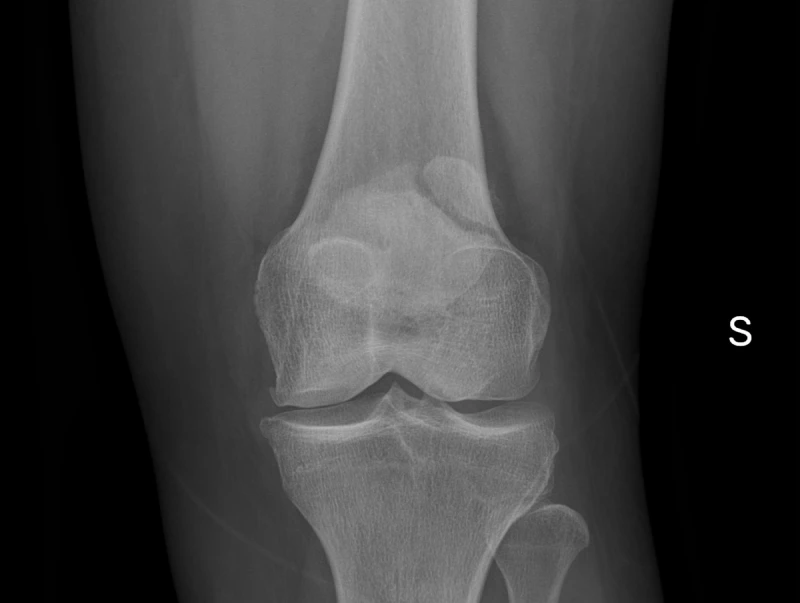

Rótula bipartita

Titulo del caso Presentación Edad: N/A Género: Femenino Discusión Diagnósticos Diferenciales Artículos